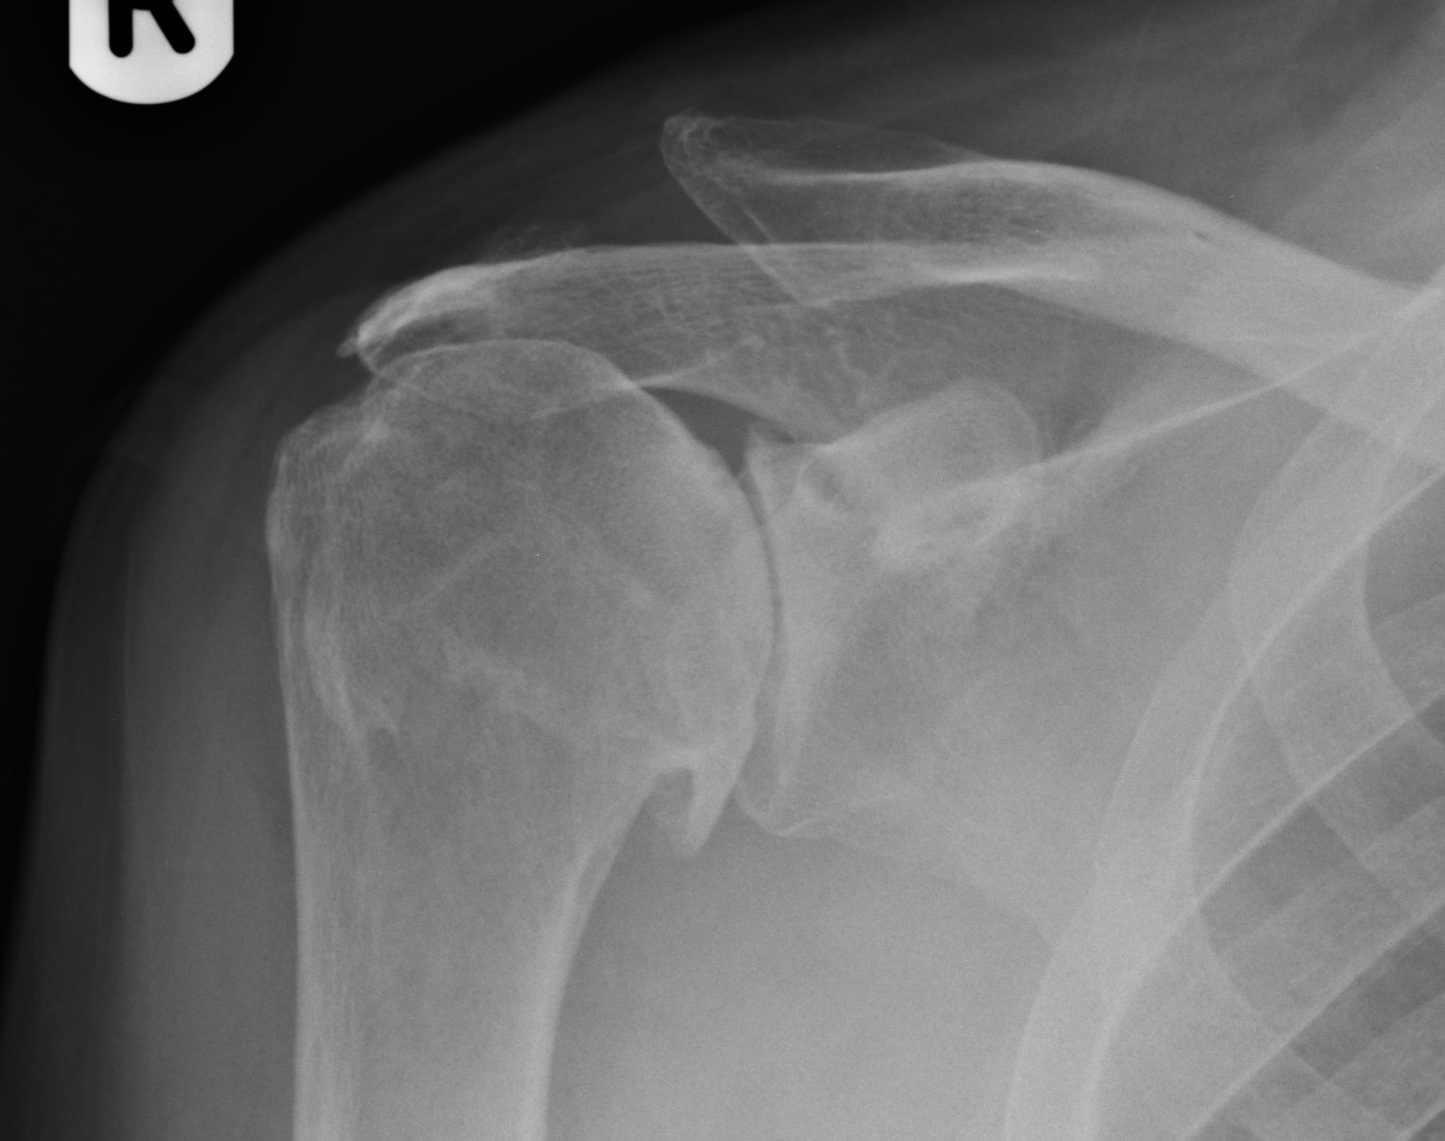

Pre operative X-ray showing a arthritic shoulder joint